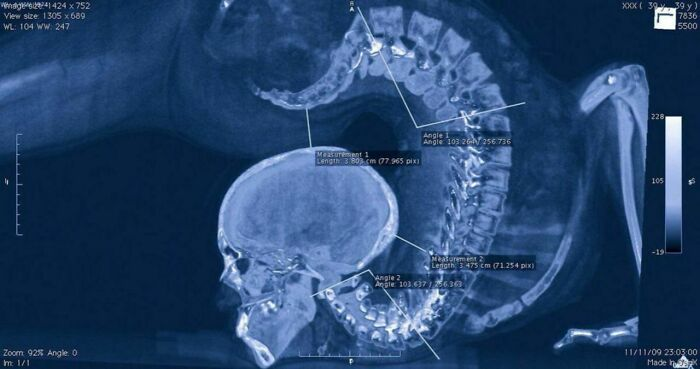

#5 체조 선수의 X레이 촬영